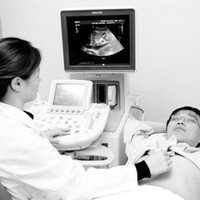

40대 사망원인 최고…간 질환의 현주소를 알자

간염, 간경변, 간암 등의 간 질환은 우리나라에서 매우 흔한 질환 중 하나이다. 2005년 발표된 2004년 사망원인 통계결과에 따르면 간 질환은 우리 국민의 사망원인 중 6위에 올라 있으며, 40대에서는 2위를 차지할 정도로 심각…

10월1일은 세계보건기구(WHO)가 정한 ‘세계 간의 날’이고 10월20일은 국내 학계가 정한 제7회 ‘간의 날’이다. 그래서 국내 의료계는 10월을 간의 달로 부르며 간 질환 홍보에 대대적으로 나섰다.대부분의 사람들은 신체에서 가…